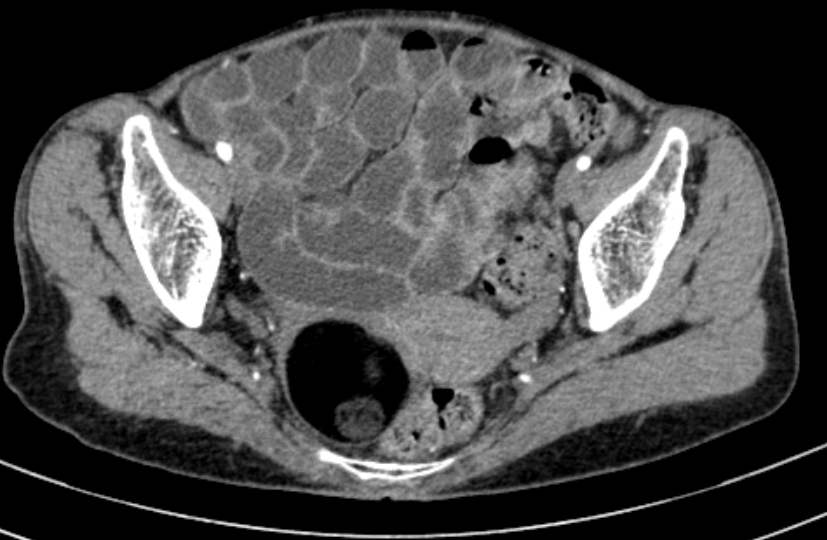

- There is a well defined right adnexal mass which contains mostly fat with two well-defined non enhancing soft tissue nodule along posterior wall and anteromedial wall. The mass measures approximately 5.1 x 4.4 x4.0 cm.

- CECT features are suggestive of right ovarian dermoid cyst

CT findings are suggestive of Right ovarian dermoid cyst.